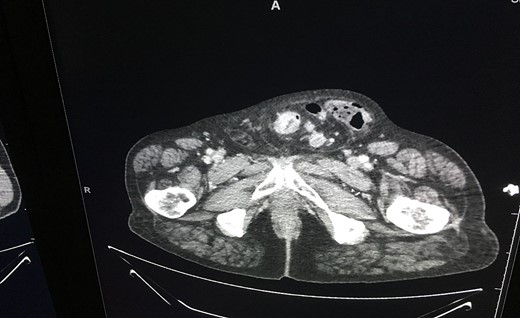

He was admitted to hospital after these investigations and his warfarin was replaced with therapeutic dose of subcutaneous enoxaparin. He had liver biopsy 4 days postadmission that confirmed metastatic disease. He was discussed at the multidisciplinary team (MDT) meeting and offered the choice of surgical intervention for his primary sigmoid tumour. After careful consideration, the patient chose the surgical option. He underwent open excision of the tumour (see Fig. 4).